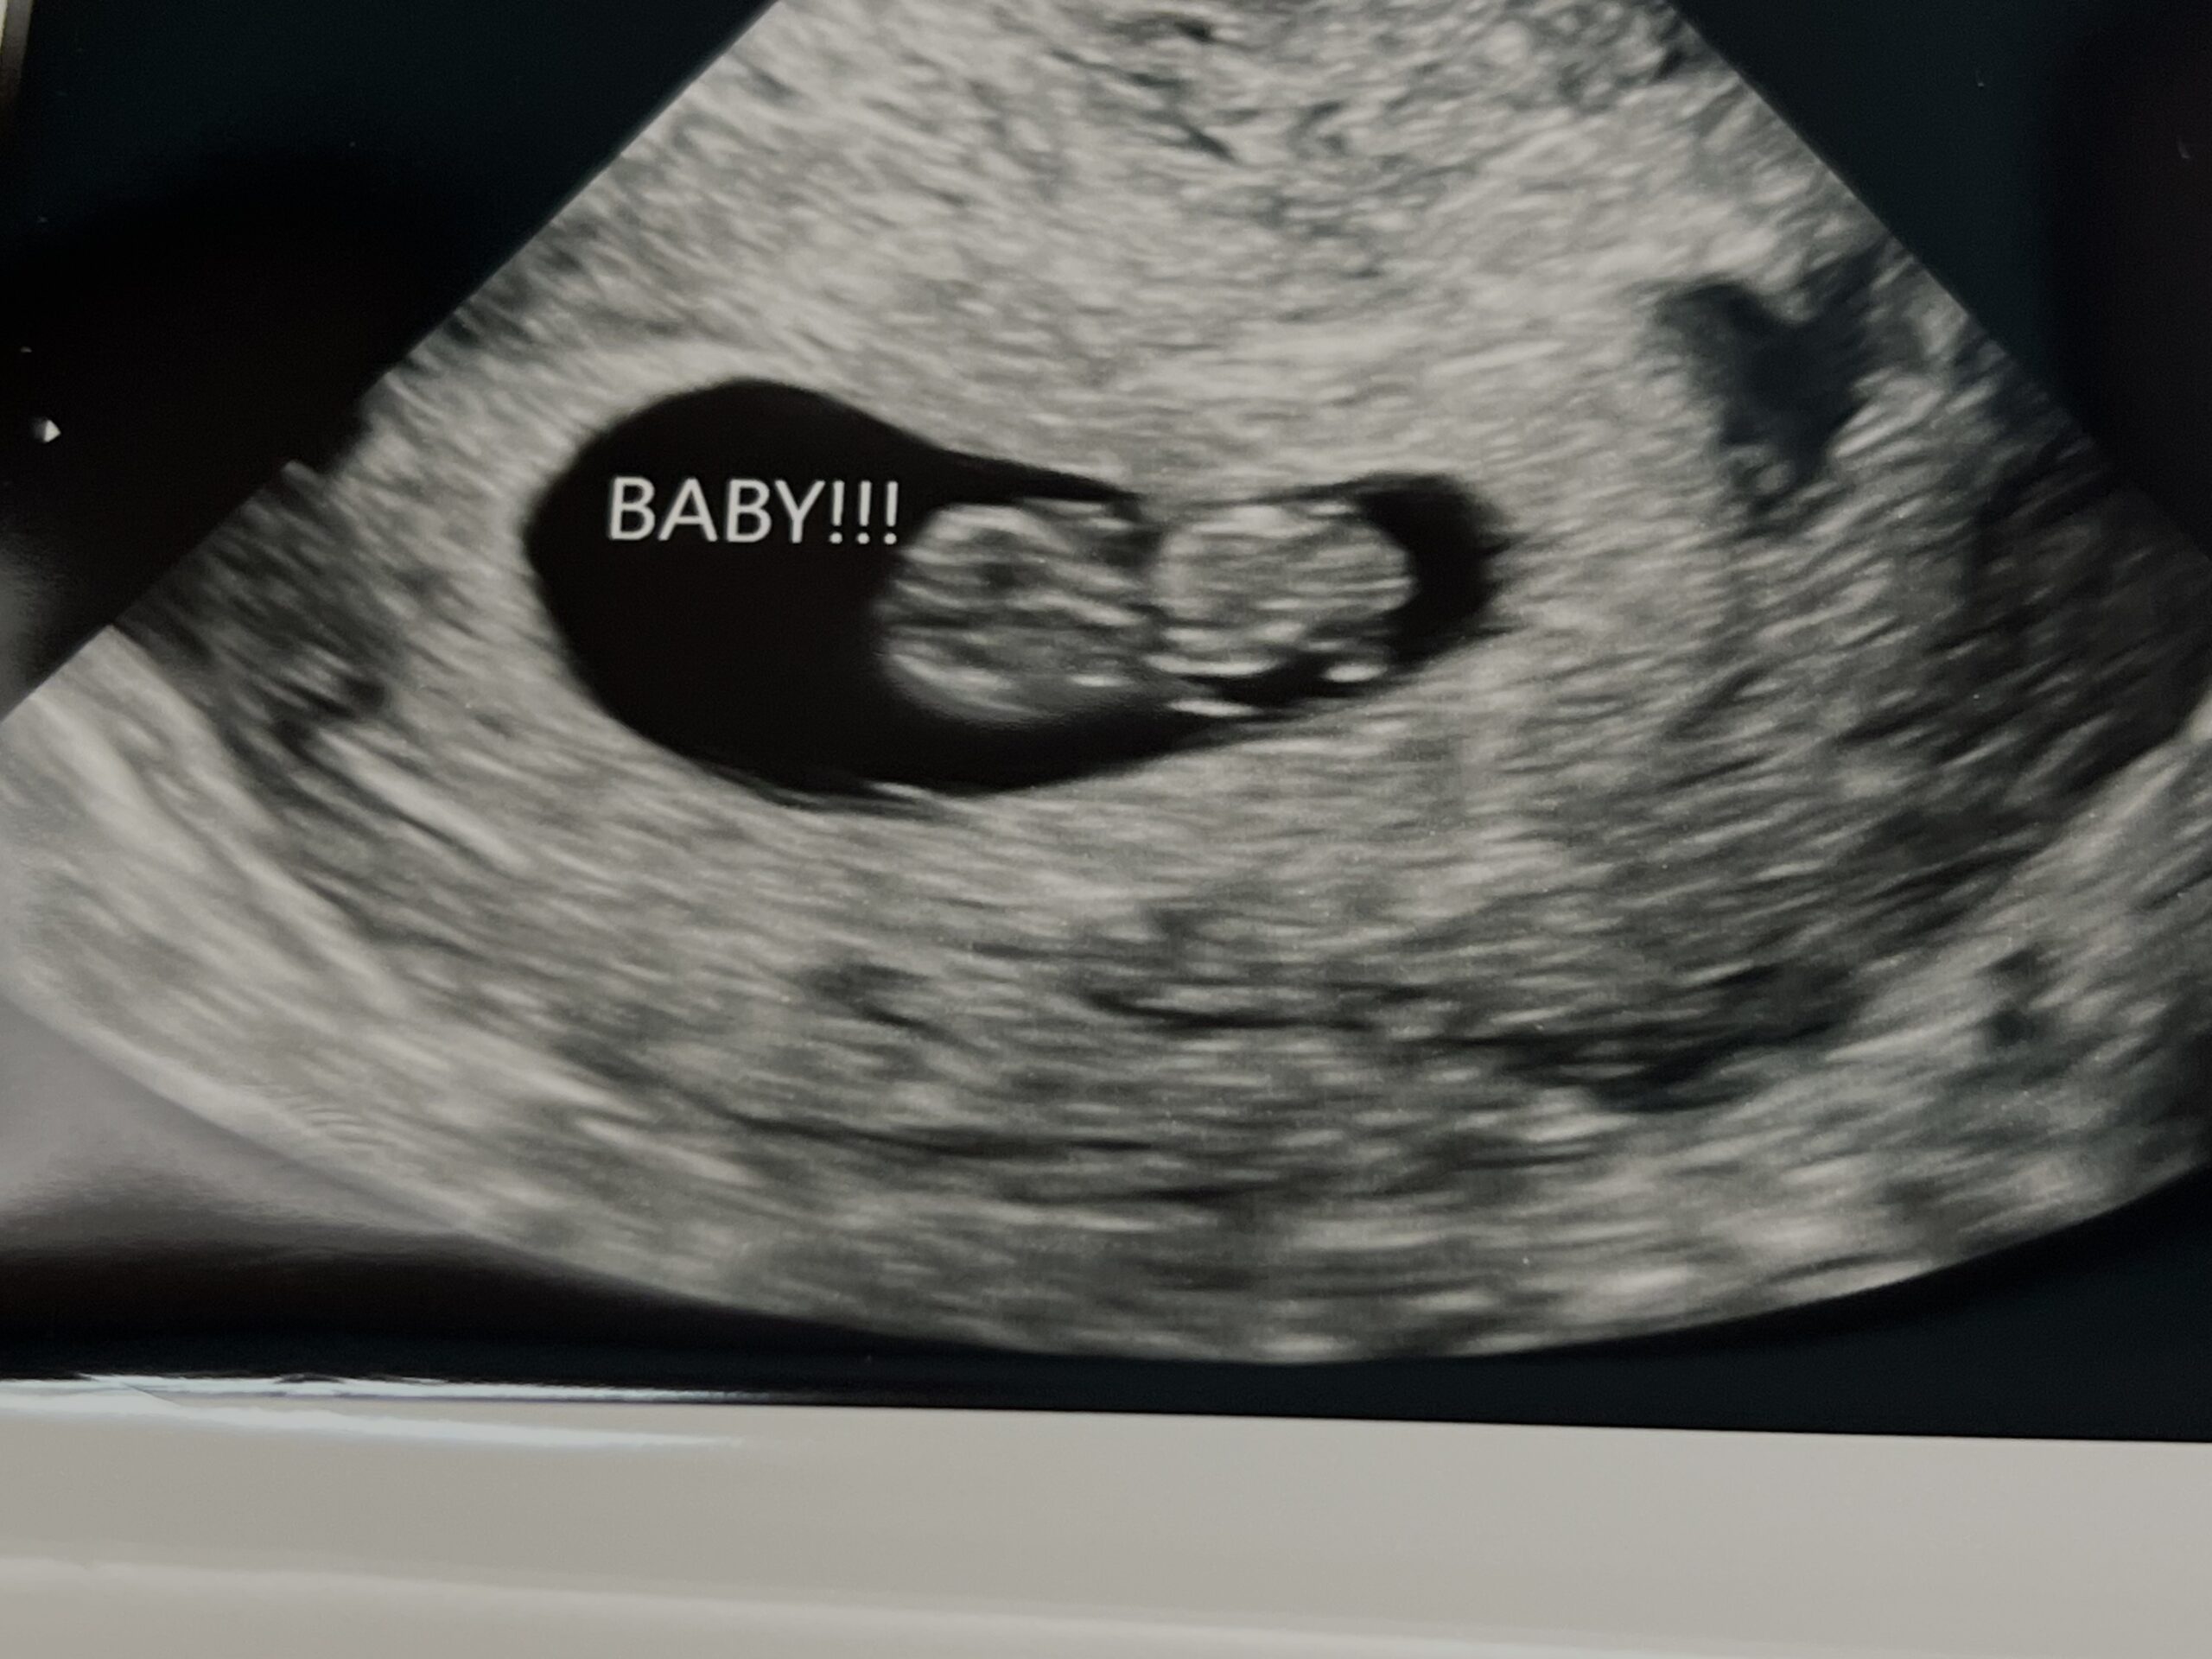

Tubal Reversal 2025, Baby 2026 On The Way

I am currently 9w4d pregnant after having my tubal reversal done by Dr. Monteith in June of 2025!

We are over the moon excited for this blessing!